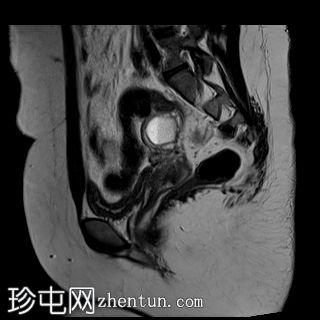

矢状位

T2加权像

双侧卵巢位置接近(卵巢相吻),左侧卵巢内可见一边界清晰的囊性病变,大小约3.1 × 2.7 × 2.9 cm,T1加权像呈高信号,T2加权像可见暗点征及内部暗点征。以上MRI特征符合卵巢子宫内膜异位囊肿的诊断。

右侧卵巢可见一囊肿,大小约为 2.8 × 2.0 × 2.2 cm,T1 加权像呈高信号,囊内可见液-液平面,提示囊内含有不同时期的出血性物质。由于对侧卵巢存在典型的子宫内膜异位囊肿,且该囊肿无强化,影像学表现强烈提示为另一子宫内膜异位囊肿。

子宫大小、轮廓及信号强度均正常,子宫内膜分区结构完整。未见局灶性肌层病变,子宫内膜厚度在正常范围内。

双侧卵巢囊性病变,MRI 表现符合子宫内膜异位囊肿的特征,左侧较大。未见强化壁结节或实性成分,提示无恶性转化。